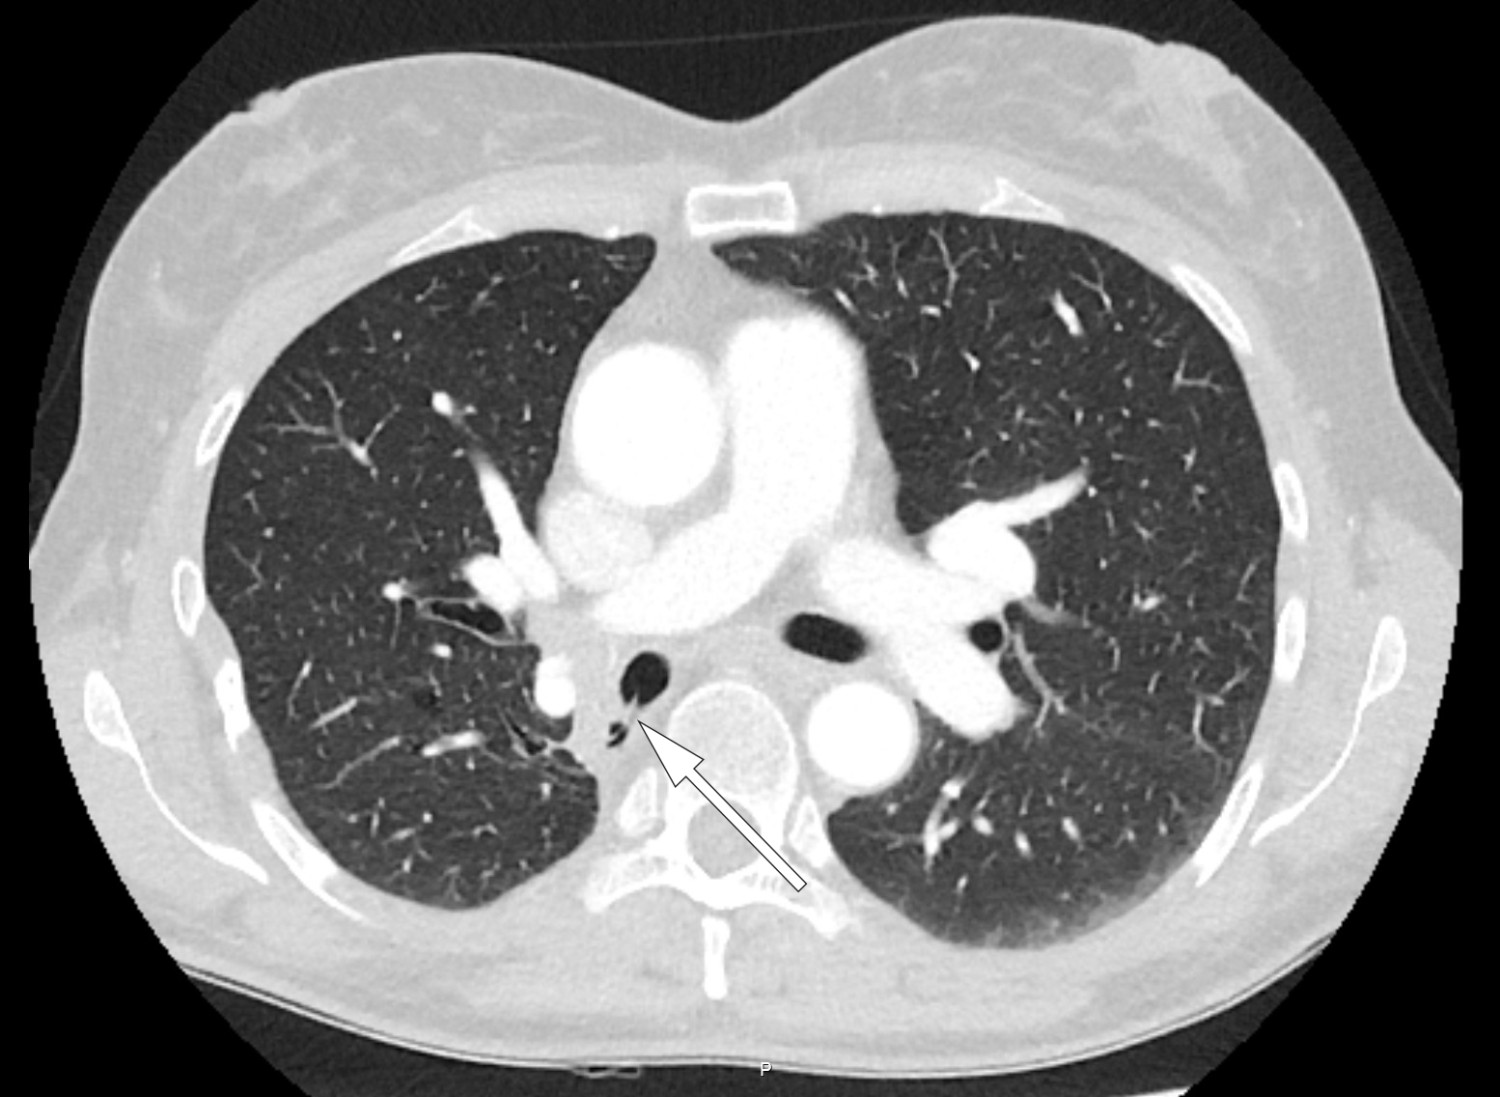

Pasienten er en kvinne i 50-årene. Som barn ble hun operert med partiell høyresidig underlappsektomi. Man lot det apikale underlappssegmentet stå igjen, og det ble brukt ikke-resorberbar tråd. Etter operasjonen har hun hatt tilbakevendende nedre luftveisinfeksjoner, alt fra bronkitt til pneumoni. Forut for den aktuelle bronkoskopien ble det gjort CT thorax som avdekket abscessutvikling (CT-bilde). Ved utredning fant man ingen underliggende immunsvikt eller andre forklaringer på infeksjonstendensen. Hun røyker daglig, men har ingen obstruktiv lungesykdom. Suturmaterialet som ble avdekket ved bronkoskopi var i retrospekt synlig på CT thorax-bildet, men kunne muligens mistolkes som sekret i luftveiene.

Suturmateriale er som et fremmedlegeme og fremmer dannelse av en biofilm og bakteriekolonisering. Dette er høyst sannsynlig årsaken til gjentatte pneumonier og utviklingen av lungeabscess (1). De synlige suturene lot seg fjerne med tang bronkoskopisk. Prosedyren ble gjort først etter at pasienten hadde gjennomført langvarig antibiotikabehandling. Selv om det hadde gått mer enn 40 år siden operasjonen fant sted, var ikke suturmaterialet brutt ned. I litteraturen har vi funnet bare få rapporter om fjerning av aspirert fremmedlegeme med tilsvarende tidsspenn fra aspirasjon til fjerning (2). I disse tilfellene har indikasjonen for utredningen vært tilbakevendende pneumonier, slik som hos vår pasient. Det vi kan lære av kasuistikken, er at hos pasienter med gjentatte nedre luftveisinfeksjoner av ukjent årsak bør man vurdere CT thorax og bronkoskopi.